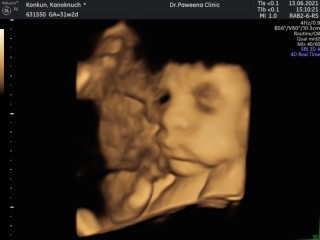

สอบถามแม่ๆหน่อยค่ะ ช่วยดูหน่อยค่ะ ว่าน้องมีภาวะปากไม่ปกติหรือป่าวคะ เครียดมากเลยค่ะ แม่ดูยังไงก็แปลกๆ แต่คุณหมอบอกปกติดี เครียดมากจริงๆค่ะ#ท้องแรกค่ะ #ขอบคุณล่วงหน้านะคะ #35w2314g

ถ้าคุณหมอบอดปกติต้องเชื่อคุณหมอนะคะ ในภาพมีน้ำคร่ำอยู่บ้างไม่ได้ชีดไปสะหมด เราไม่ได้เป็นหมอก็ต้องเชื่อหมอไม่ควรคิดมาก

ปกตินะคะ ปากเจ่อน่ารักดีค่ะ หมอคือผู้เชี่ยวชาญ ถ้าเราไม่วางใจในตัวคุณหมอ เราจะวางใจกับใคร คุณแม่อย่าคิดมากคะ

มันเป็นที่มุมค่ะ บ้านนี้เห็นก็ตกใจคุณหมอบอกน้องปกติมันเป็นด้านข้างเลยเห็นไม่ชัด

น้องปกตินะค่ะอย่าเครียดเลยค่ะ ภาพมันไม่ได้ชัดเสมอไป

น่าจะเป็นที่มุมกล้องมากกว่าค่ะแม่ น้องน่าจะปกติค่ะ

น้องอยู่ในน้ำคล่ำเลยดูแปลกๆหน่อย อย่าเครียดค่ะแม่